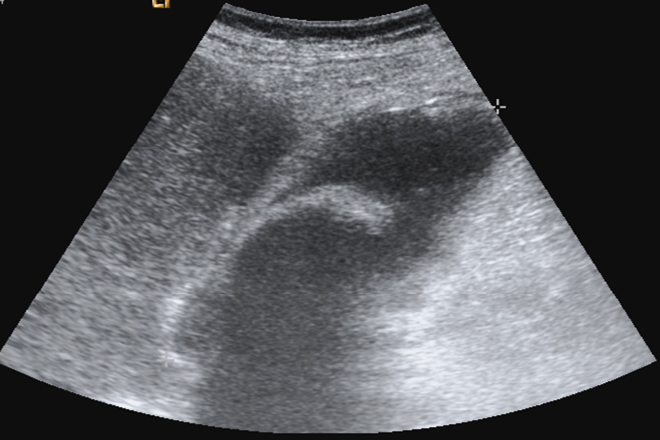

Ultrasonido en el primer trimestre de embarazo

Es importante que el médico de primer contacto aprenda a utilizar e interpretar ultrasonido, ya que proporciona la confirmación de un diagnóstico, pronostica como será el proceso y la culminación de un embarazo. El Artículo proporciona 10 recomendaciones para la evaluación ultrasonográfica del primer trimestre de embarazo en el primer